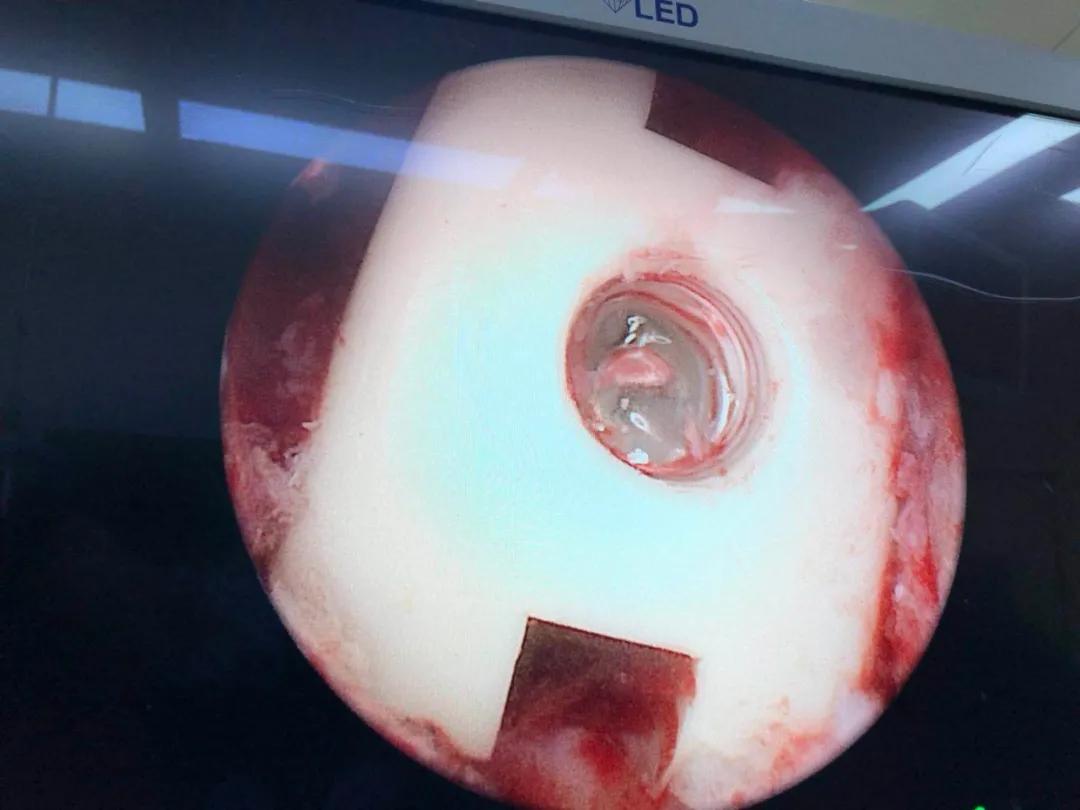

海安市中医院副院长、骨伤科主任魏爱淳主任中医师接诊后,为其制定了UBE(单侧双通道内镜微创技术)治疗方案。做好各项术前准备后,魏爱淳副院长、蒋剑锋主任和他们的手术团队在专家指导下,采用UBE专用综合器械包和专用等离子射频手术系统,成功为患者实施了UBE技术下L3/4椎管减压,L4/5椎管减压、椎间植骨融合术,手术只有5个微创小切口,术后江先生的双下肢疼痛、麻木症状缓解,手术达到预期的效果,获得了患者及家属的一致称赞。

据了解,相比传统的单通道椎间孔镜技术,UBE技术的手术视野和操作空间更广泛,适用于多种类型的腰椎间盘突出症、椎管狭窄症及轻度的腰椎滑脱症,是一项新兴的脊柱微创技术,术中清晰的镜下视野,配合熟练的器械操作,使得椎管减压和椎间融合过程在少剥离、少出血、高效率的条件下顺利完成。